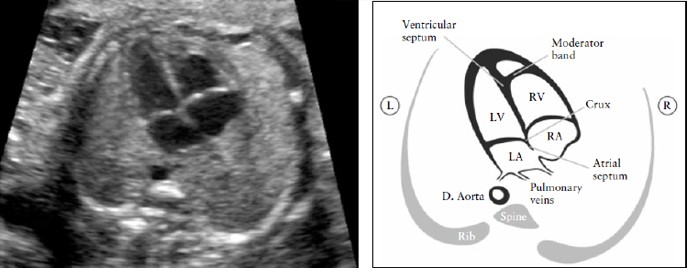

Рисунок 2. Четырех-камерный срез сердца. Ключевые элементы этого среза во втором триместре: сердце занимает не более 1/3 грудной клетки, правые и левые отделы сердца почти одинаковые по размеру (размер камер и толщина стенок), клапан овального окна открывается в левое предсердие, интактный ” крест” сердца с нормальным смещением двух атриовентрикулярных клапанов и интактная межжелудочковая перегородка.

Морфологически правый желудочек идентифицируется наличием модераторного пучка и трикуспидальным клапаном, который располагается более апикально по отношению к митральному клапану. D. Aorta- нисходящая аорта ; L- левый; LV-левый желудочек; R- правый; RA- правое предсердие

Дефекты межжелудочковой перегородки (ДМЖП) могут быть сложно диагностируемыми. Перегородку лучше всего видно, когда угол инсонации перпендикулярен ей. Когда же ультразвуковой луч непосредственно параллелен стенке желудочка, дефект может быть ложно заподозрен по причине акустического артефакта.

Небольшие ДМЖП (1-2 мм) часто очень сложно верифицировать, когда ультразвуковой аппарат не обеспечивает достаточную степень разрешения, и особенно если расположение плода не является благоприятным. Однако, в большинстве случаев, они имеют ограниченное клиническое значение и даже могут спонтанно закрываться внутриутробно [59,60].

Два отдельных атриовентрикулярных клапана (правосторонний – трехстворчатый клапан; левосторонний – митральный клапан) должны визуализироваться свободно и самостоятельно двигающимися. Септальная створка трехстворчатого клапана прикреплена несколько ближе к верхушке по сравнению со створкой митрального клапана (т.е. нормальное смещение – offset). Аномальное прикрепление атриовентрикулярных клапанов может быть ключевой эхографической находкой для определения пороков сердца, таких как атриовентрикулярный септальный дефект (атриовентрикулярный канал).